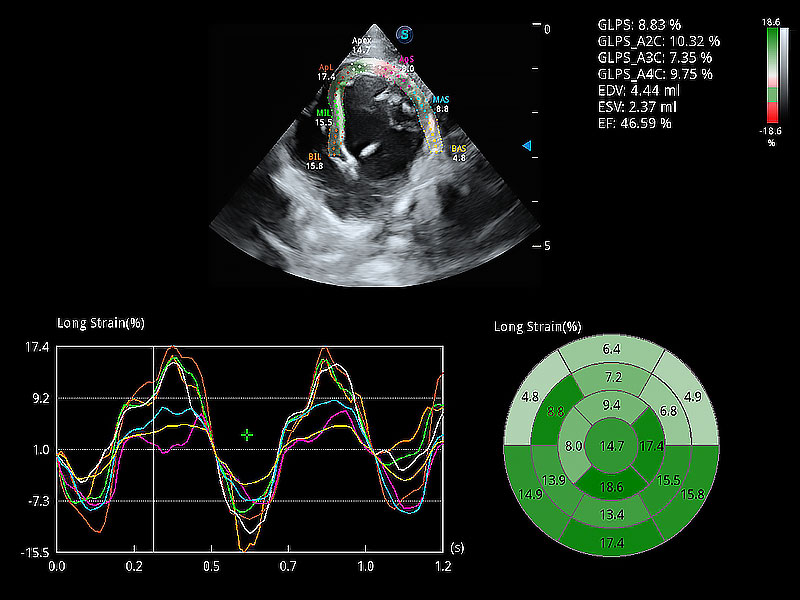

通過(guò)心肌識(shí)別技術(shù)與二維斑點(diǎn)追蹤技術(shù)相結(jié)合,對(duì)心臟的超聲圖像進(jìn)行量化分析。計(jì)算心肌17個(gè)節(jié)段的應(yīng)變、應(yīng)變率、速度、位移等,并通過(guò)牛眼圖的形式進(jìn)行呈現(xiàn)。

實(shí)時(shí)用顏色表示心肌組織運(yùn)動(dòng),觀察和定量組織的運(yùn)動(dòng)情況,對(duì)快速檢測(cè)與評(píng)估心肌的灌注和活性、電傳導(dǎo)及心肌收縮和舒張功能等均能提供重要的診斷信息。